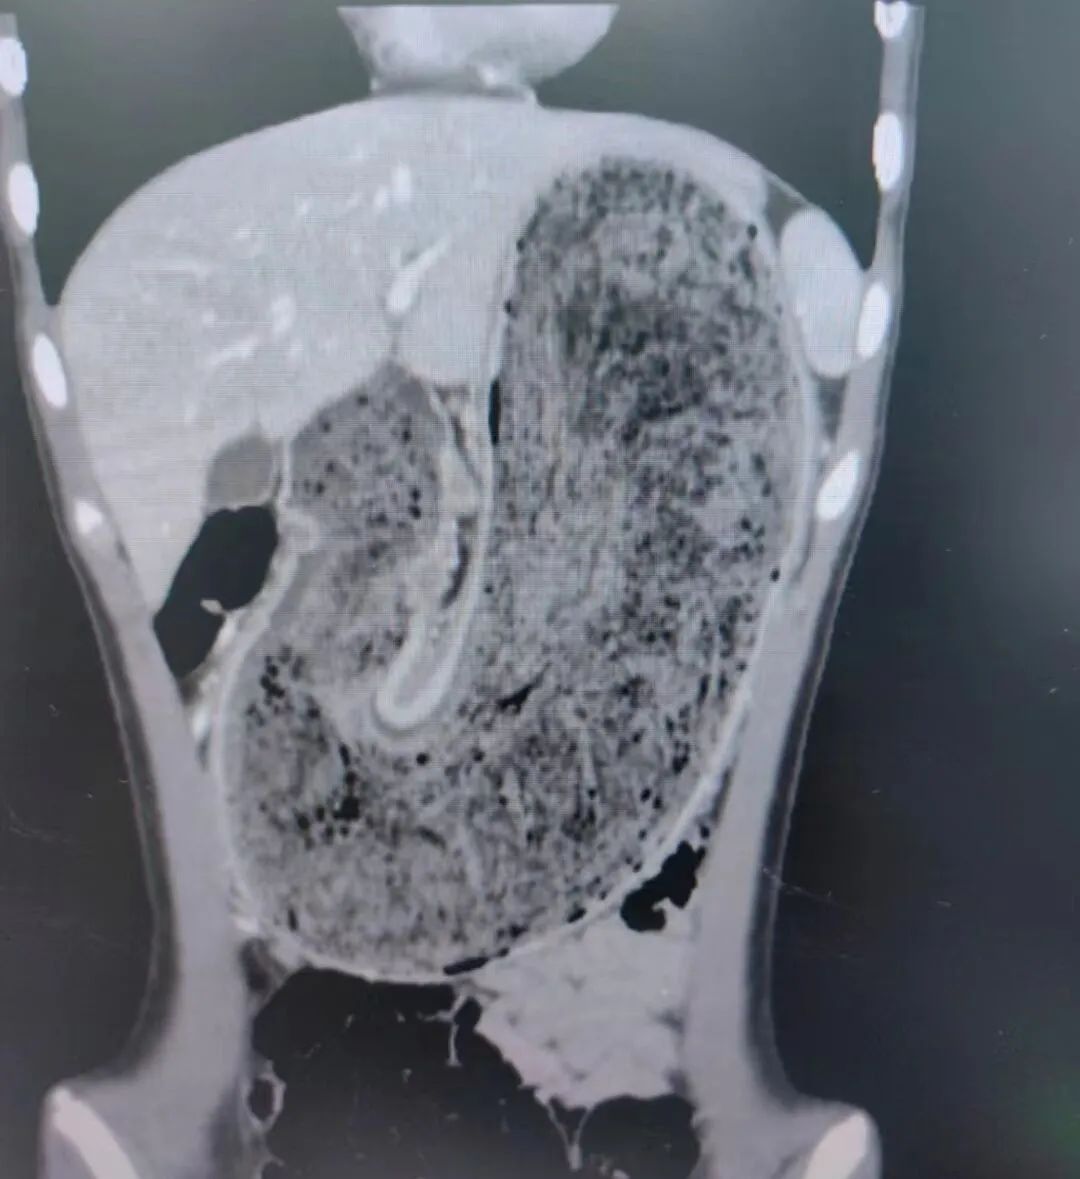

▲欢欢的胃腔里有大块的毛絮状结石

随后,他们将女儿送到东莞市妇幼保健院。内科医生张铭承接诊后对欢欢进行检查,结果惊讶地发现,欢欢的胃腔和肠管里有大块的毛絮状结石,几乎占据整个胃部——这就是腹痛的根源。